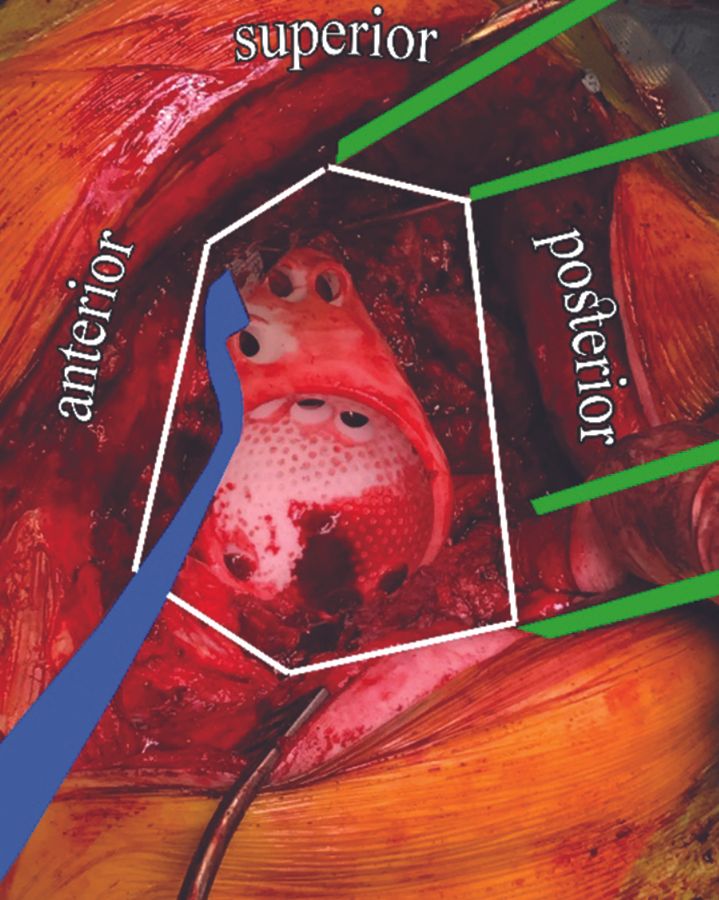

In our clinic all operations with patient matched implants are performed by two senior orthopaedic surgeons only. They use a posterolateral approach and removal of a fixed femoral component is not mandatory but can be helpful for optimal exposure in selected cases. The femur is moved and held anteriorly with a large Hohmann retractor. A posterior soft tissue envelope is created by carefully releasing the posterior capsule form the posterior wall and ischium protecting the ischial nerve. A Cobb elevator can be helpful for exposure. Steinmann pins or threaded Kirschner wires are inserted maintaining the exposure. Afterwards the anterior structures are released starting superior with the caput reflexum of the rectus toward the pubic bone inferiorly. The gluteus maximus insertion is often released. Now the entire acetabular defect including the surface for flanges on the ilium, ischium, and pubic bone is exposed through a moveable window (figure 6). This window can be moved anterior, posteriorly, superiorly and inferiorly wherever exposure is needed during surgery.

The original acetabular implant has to be extracted completely with all hardware and cement. 6 cultures are obtained from multiple locations in every revision. Osteophytes have to be removed according to the preoperative plan before insertion of the trial implant. Sclerotic bone surface should be cleared by an acetabular reamer, curette or drilling small drill holes. Morselized allograft bone may be used to fill remaining contained defects between implant and host bone. With the included plastic trail implant a good fitting and orientation can be controlled before insertion of the definitive implant (figure 6).

- Exposure and creating the moveable window as mentioned above is essential for good positioning of the implant (figure 6).

- Steinmann pins or threaded Kirschner wires are helpful for holding the posterior structures away and safe (figure 6).